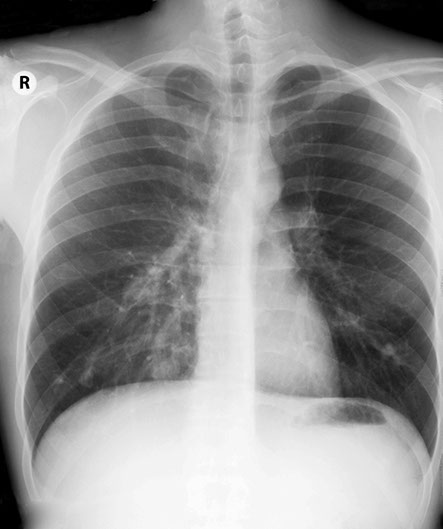

Trouble in the chest, in a lady with a stroke. Surely you can just see the outline of the oval density in the right base through the liver!

Lady with transient ischaemic attacks. Note the rounded density lateral to the right breast.

Which in the lateral projection can be clearly seen projected over the heart.